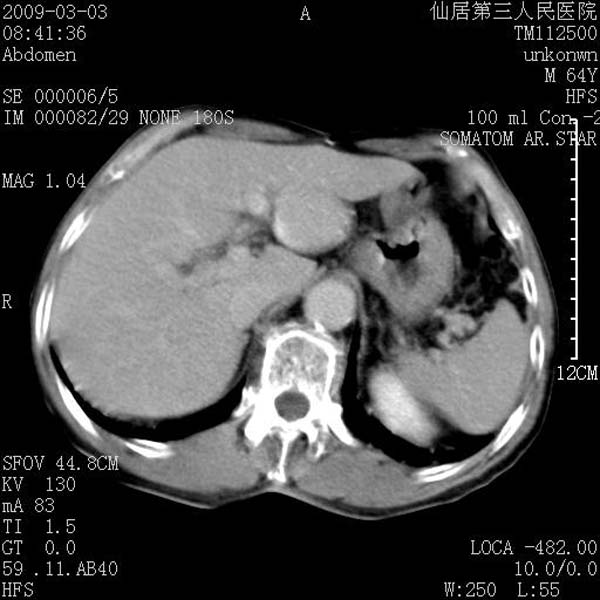

标题: CT18469:男性,64y,体检B超示肝脏低回声肿块,有胃溃疡手术 [打印本页]

患者,男性,64y,体检b超示肝脏低回声肿块,有胃溃疡手术史。

从平扫及增强的特点来看,支持肝脏腺瘤并出血。

ct值呢?感觉没强化,象囊性。

考虑肝静脉韧带裂区良性占位性病变(囊肿?)。

考虑肝囊肿并出血可能性大.

考虑高密度囊肿可能性大